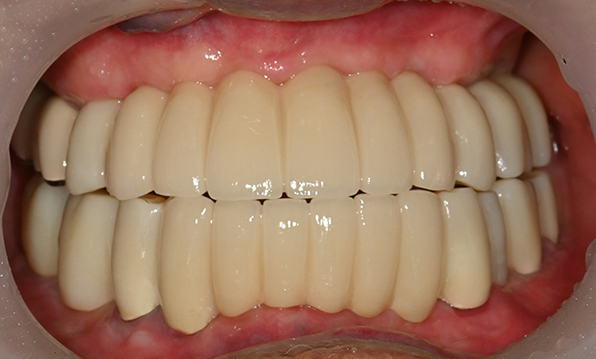

| Before | After |